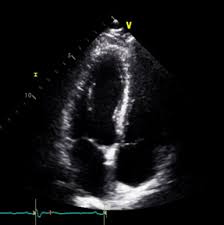

심장 초음파란 어떤 검사인가?

심장 초음파는 초음파를 이용해 심장의 크기, 움직임, 판막 상태, 혈액 흐름을 실시간으로 관찰하는 검사입니다. 방사선 노출이 없고 통증도 거의 없어 반복 검사에도 부담이 없습니다. 특히 심장 질환이 의심될 때 가장 기본적으로 시행되는 검사로, 심장 초음파로 알 수 있는 병의 범위는 생각보다 매우 넓습니다.

심장 초음파로 알 수 있는 병 ① 심부전

심부전은 심장이 혈액을 충분히 펌프질하지 못하는 상태입니다. 심장 초음파를 통해 심장의 수축력(박출률)을 측정함으로써 심부전 여부를 확인할 수 있습니다. 호흡곤란, 쉽게 피로해지는 증상이 있다면 심장 초음파로 알 수 있는 병 중 가장 먼저 확인해야 할 질환입니다.